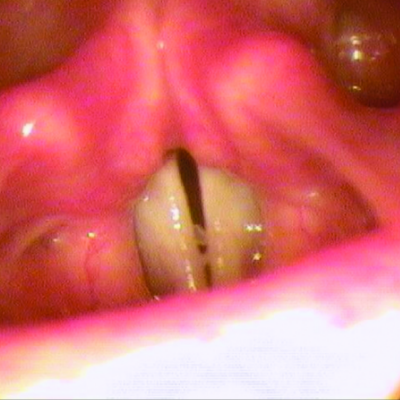

• Tissue Sloughing: If you have mucosal lesions in your respiratory tract, especially the tracheobronchial tree, and are treated with RYPLAZIM, respiratory distress may occur due to tissue sloughing. Please monitor appropriately.